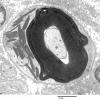

PERIPHERAL NEUROPATHY

3 NORMAL MYELIN & SCHWANN CELLS